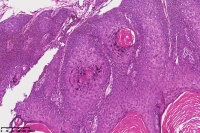

脂溢性角化症伴皮角?

性别

女

年龄

49岁

手臂皮肤组织

图1

脂溢性角化病